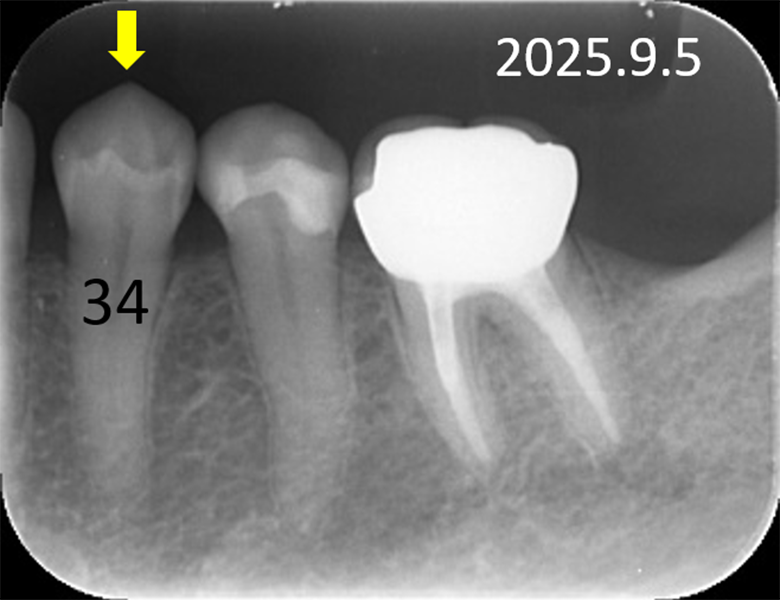

症例③ 下顎小臼歯 小窩や裂溝の虫歯 54歳女性

初診時口腔内写真 |

![]() 初診時レントゲン写真 |

約3年後の口腔内写真 |

![]() 約3年後のレントゲン写真 |

症例③

主訴 |

正しい口腔ケアを知り、健康的になりたい。 |

診断 |

下小臼歯の初期虫歯 |

治療 |

経過観察 |

期間 |

経過観察中 |

費用 |

0円 |

治療リスク |

虫歯進行の可能性 |